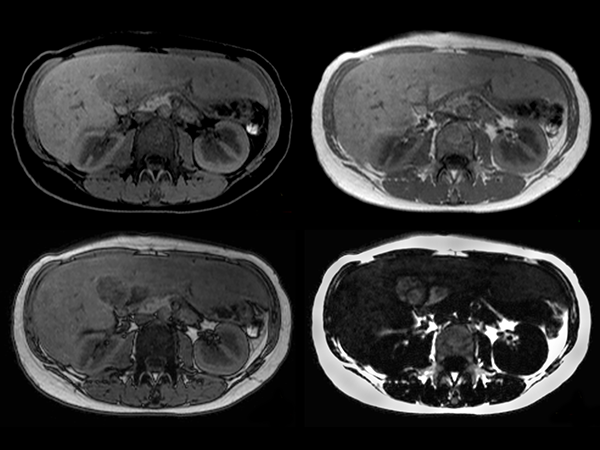

mDIXON (water only, in-phase, out-phase, fat only)